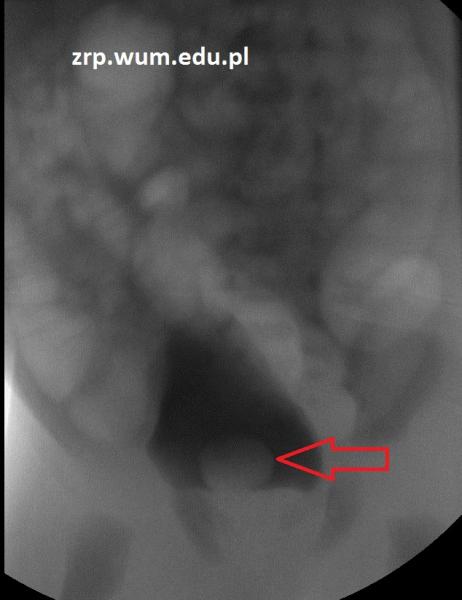

Rozpoznanie: Na zdjęciu RTG klatki piersiowej stwierdzono poszerzenie cienia śródpiersia po stronie lewej, w rzucie lewej wnęki. W trakcie dalszej diagnostyki rozpoznano chłoniaka.